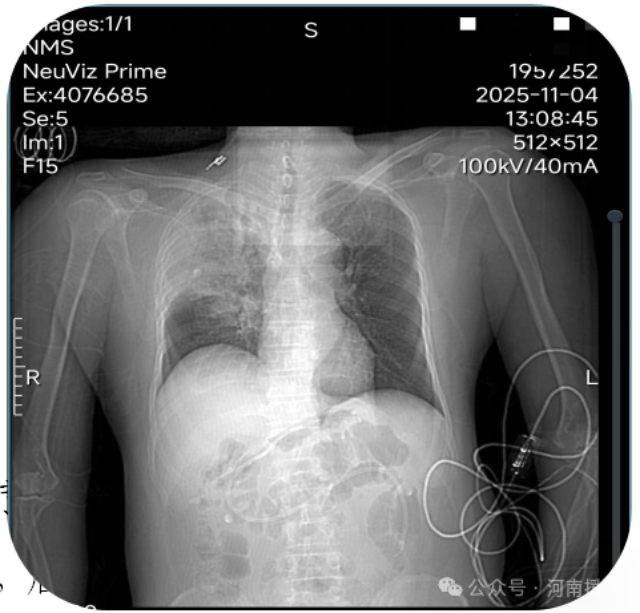

ECMO治疗前后患者胸部对比